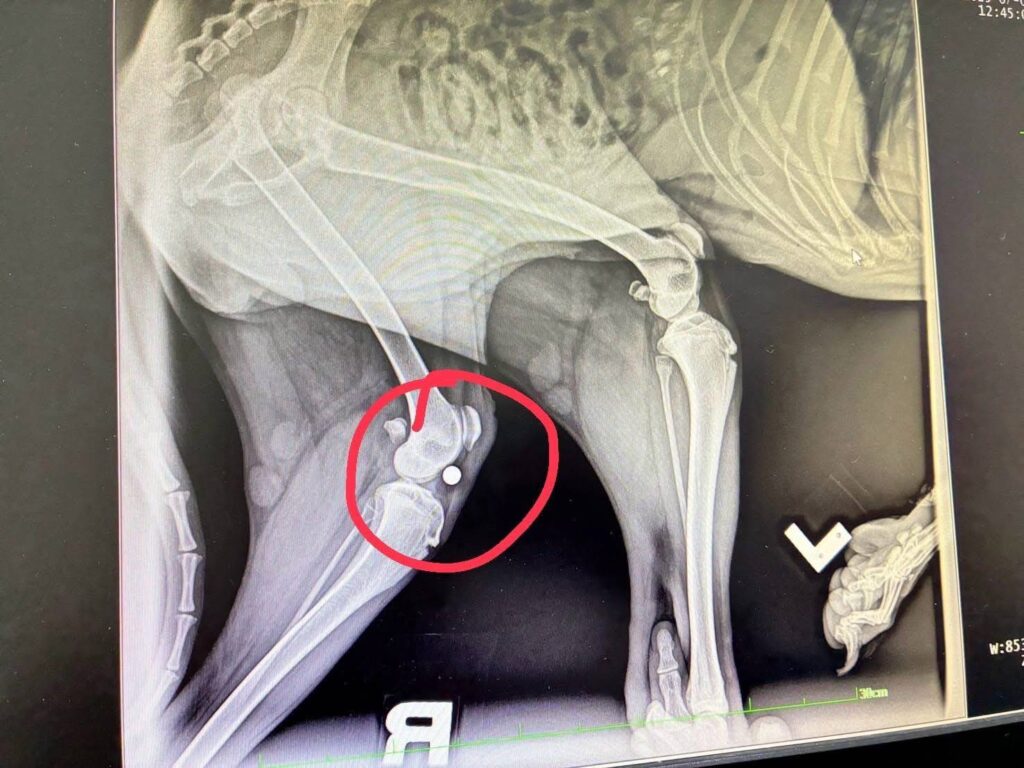

เชียงใหม่-พระครูอ๊อดติดตามใกล้ชิดกรณีช่วยเหลือสุนัขร็อตไวเลอร์ถูกทิ้งกลางป่า 1 ใน 4 บาดเจ็บสาหัส ความคืบหน้าจากการช่วยเหลือ พบกระสุนฝังในร่างกาย ต้องทำการรักษาทางการแพทย์อย่างเร่งด่วน

เมื่อวันที่ 1 กรกฎาคม 2568 พระครูสังฆรักษ์วีรวัฒน์ วีรวฑฺฒโน (พระครูอ๊อด) วัดเจดีย์หลวงวรวิหาร จังหวัดเชียงใหม่ เปิดเผยว่า ได้รับรายงานจากมูลนิธิ ดิอาร์ค ในพระราชูปถัมภ์ ซึ่งรับดูแลสุนัขพันธุ์ร็อตไวเลอร์จำนวน 4 ตัวที่ถูกนำไปทิ้งไว้กลางป่าในสภาพหิวโซและมีอาการบาดเจ็บหลายแห่ง โดยหนึ่งในสี่ตัวนั้นอยู่ในอาการบาดเจ็บสาหัส ล่าสุดเจ้าหน้าที่เไดมูลนิธิฯได้ทำการตรวจพบโลหะคล้ายกระสุนฝังอยู่ในร่างกายและอยู่ระหว่างดำเนินการผ่าตัดนำออกอย่างเร่งด่วน